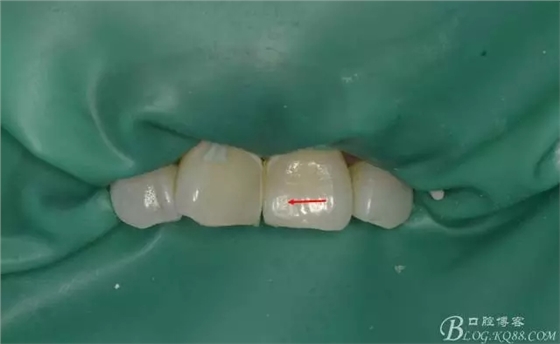

一周后復(fù)診即刻照:

(脫礦情況好轉(zhuǎn),但仍有部分釉質(zhì)仍未恢復(fù))

此案例中,酸蝕出現(xiàn)過度后,我沒有予以含氟涂料進(jìn)行處理,所以通過這個(gè)案例,驗(yàn)證了上述的學(xué)者的部分研究,即使修復(fù)后有脫礦,可不予處理,其在口腔中通過表面摩擦及口腔唾液環(huán)境中再礦化這兩種途徑,輕度脫鈣浸蝕的恢復(fù)。